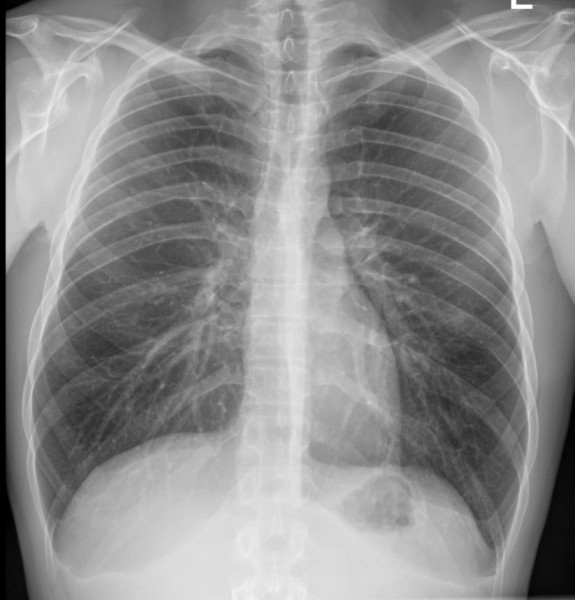

Wczoraj spadłem z ok dwóch metrów lewym bokiem na metalowe belki. Cały impet uderzenia przyjęła klatka piersiowa. Na chwilę straciłem oddech, ale potem wszystko wróciło do normy, pozostał tylko ból żeber. Dzisiaj ból się nasilił i poszedłem do lekarza no i zrobiono mi zdjęcie RTG. Niestety na konsultację z chirurgiem muszę dosyć długo czekać...a ból jest podczas zwykłych czynności i nasila się podczas głębokiego oddychania, kaszlu, "pociągania" nosem...ogólnie ból sprawia wszystko co powoduje "ruch" żeber.

Dotykowi żeber po lewej stronie również towarzyszy ból. Leżeć na obolałym boku jak i na plecach nie mogę bo ból temu towarzyszący jest nie do wytrzymania,

Czy mógłbym prosić o ocenę zdjęcia czy udać się z tym na SOR czy czekać posłusznie na wizytę u dr chirurga?

zdj2.jpg

Zdj1.jpg